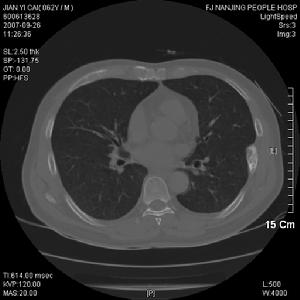

2、影像學表現

二、X線上,病灶的密度常有差異,取決於病理成分,病灶如主要為纖維組織常表現為囊狀透光區;如主要為砂礫樣鈣化新生骨者常呈磨砂玻璃狀;如新生骨鈣化較多時則表現為一片明顯的增白區。每一病灶,可以上述表現按不同比例組合出現。

骨纖維異常增殖症①變形性骨炎型:常為多骨型病變表現,其特點是顱骨增厚,顱骨外板和頂骨呈單側泡狀膨大,骨內板向板障和顱腔膨入,增厚的顱骨中常見局限和瀰漫的射線透明區和濃密區並存,這種骨吸收與硬化並存極似Paget變形性骨炎的表現。顱骨擴大和硬化,可從額骨擴大到枕骨。面部受累可導致眶和鼻腔狹窄及鼻竇腔消失,此型約占56%。②硬化型:此型多見上頜肥厚,可致牙齒排列不整,鼻腔、鼻竇受壓變小。上頜骨受累多於下頜骨,且多為單骨型。損害呈硬化或毛玻璃樣外觀。相反,下頜骨損害多見於多骨型,表現為孤立的骨壁光滑且可透過射線。此型約占23%。③囊型:顱骨呈孤立或多發的環形或玫瑰花形缺損,缺損從菲薄的硬化緣開始,其直徑可達數厘米。孤立的損害有似嗜酸性肉芽腫,多發的缺損可誤認為HandSchüllerChristian病,偶有數種X線類型出現於同一個體上。此型約占21%。套用CT或MRI檢查,能明確病變的位置和範圍,且能顯示與軟組織的聯繫。定期檢查可動態觀察病變的發展程度,對選擇術式進路、減少併發症和估計預後甚為重要。